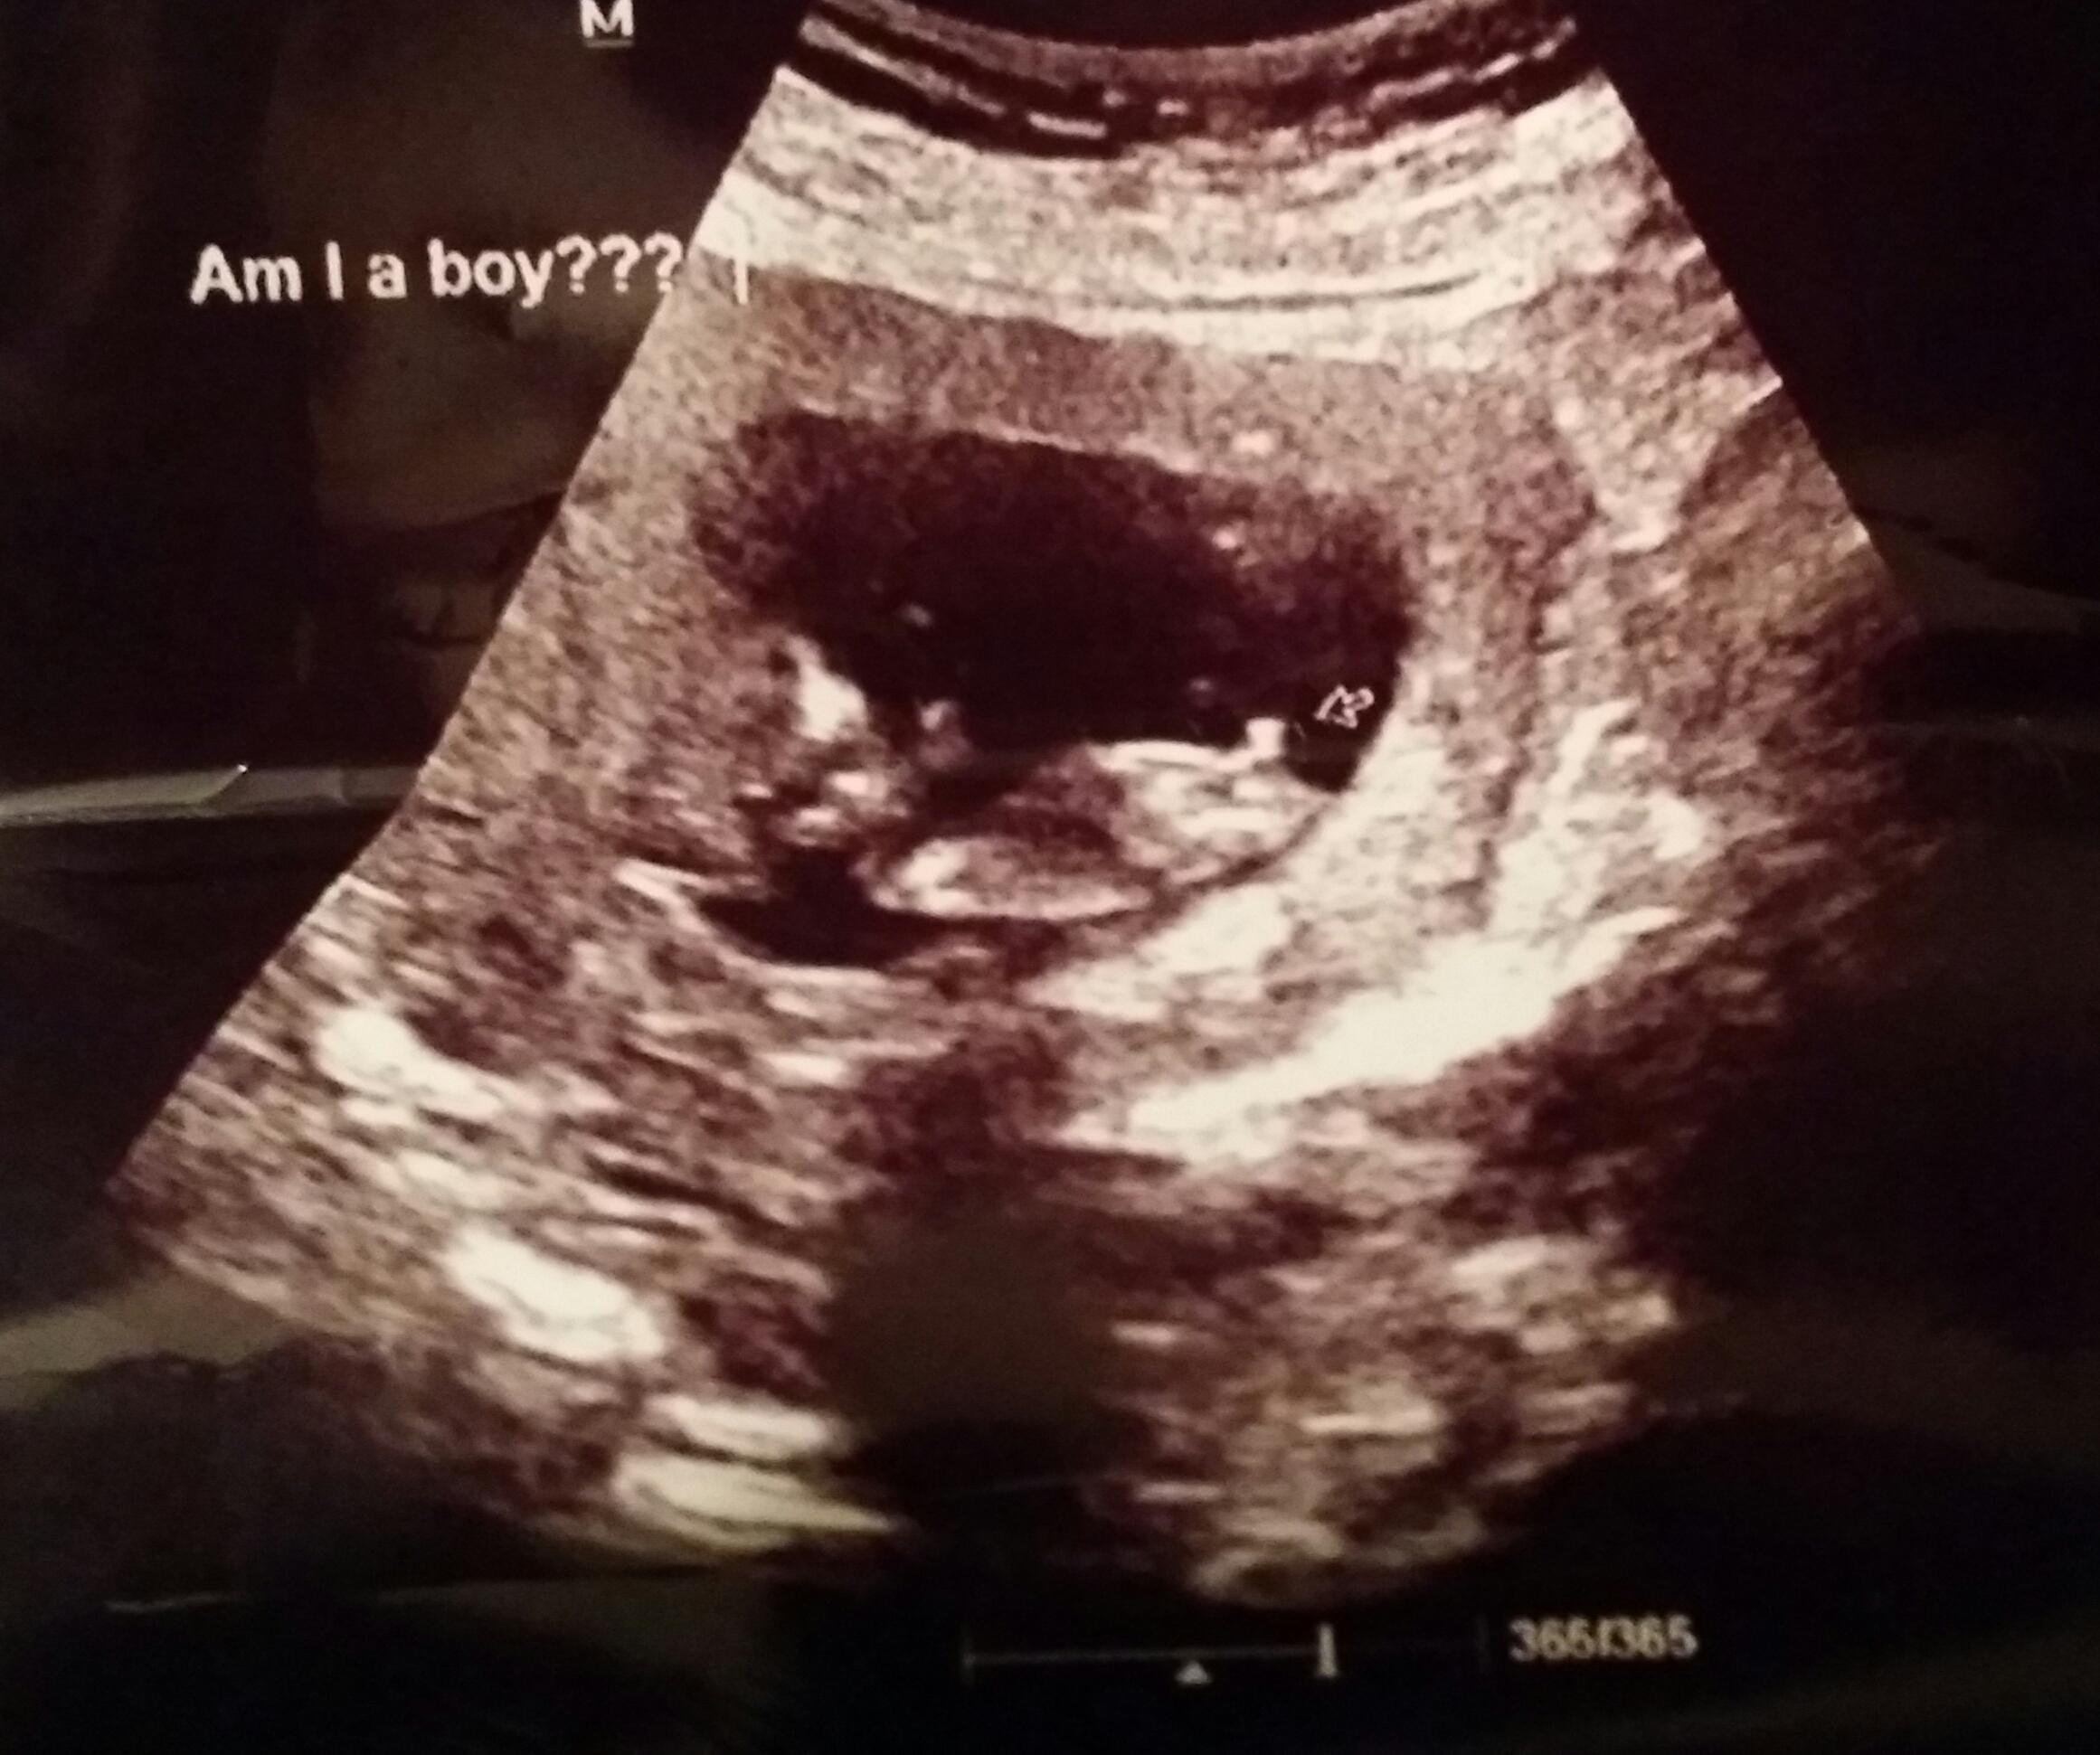

It is too early for nub guesses but looks boyish at the moment.

Early but boyish

BOY, by angle of the nub, it is raised, and the bump on the end of the nub is very boyish to me, like stacking.

looking to be a boy, but early.

Boy but early